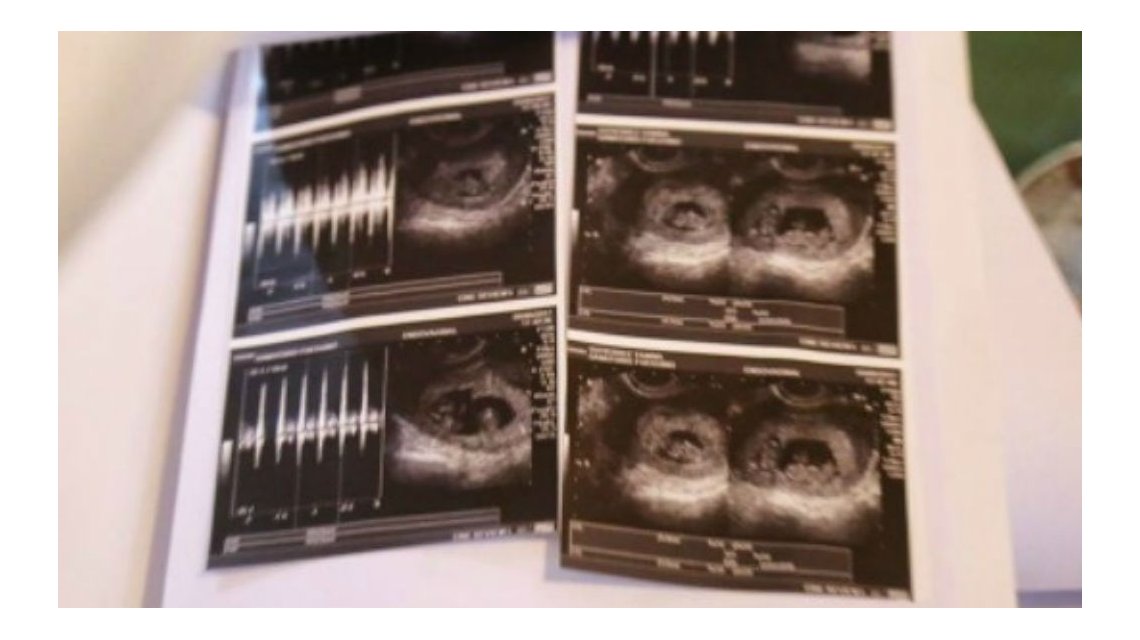

"Yo veía tres bolsitas pero como es la primera vez que transitamos esto no sabíamos de qué se trataba por eso nos quedamos callados", contó Yanina en los medios.

Y, el médico me dijo: ‘No, son más’. ¡Trillizos!, pensamos nosotros y el doctor nos terminó confirmando: ‘¡Son cuatro: en cada punta están los mellizos y en el medio los gemelos!", relató la joven.